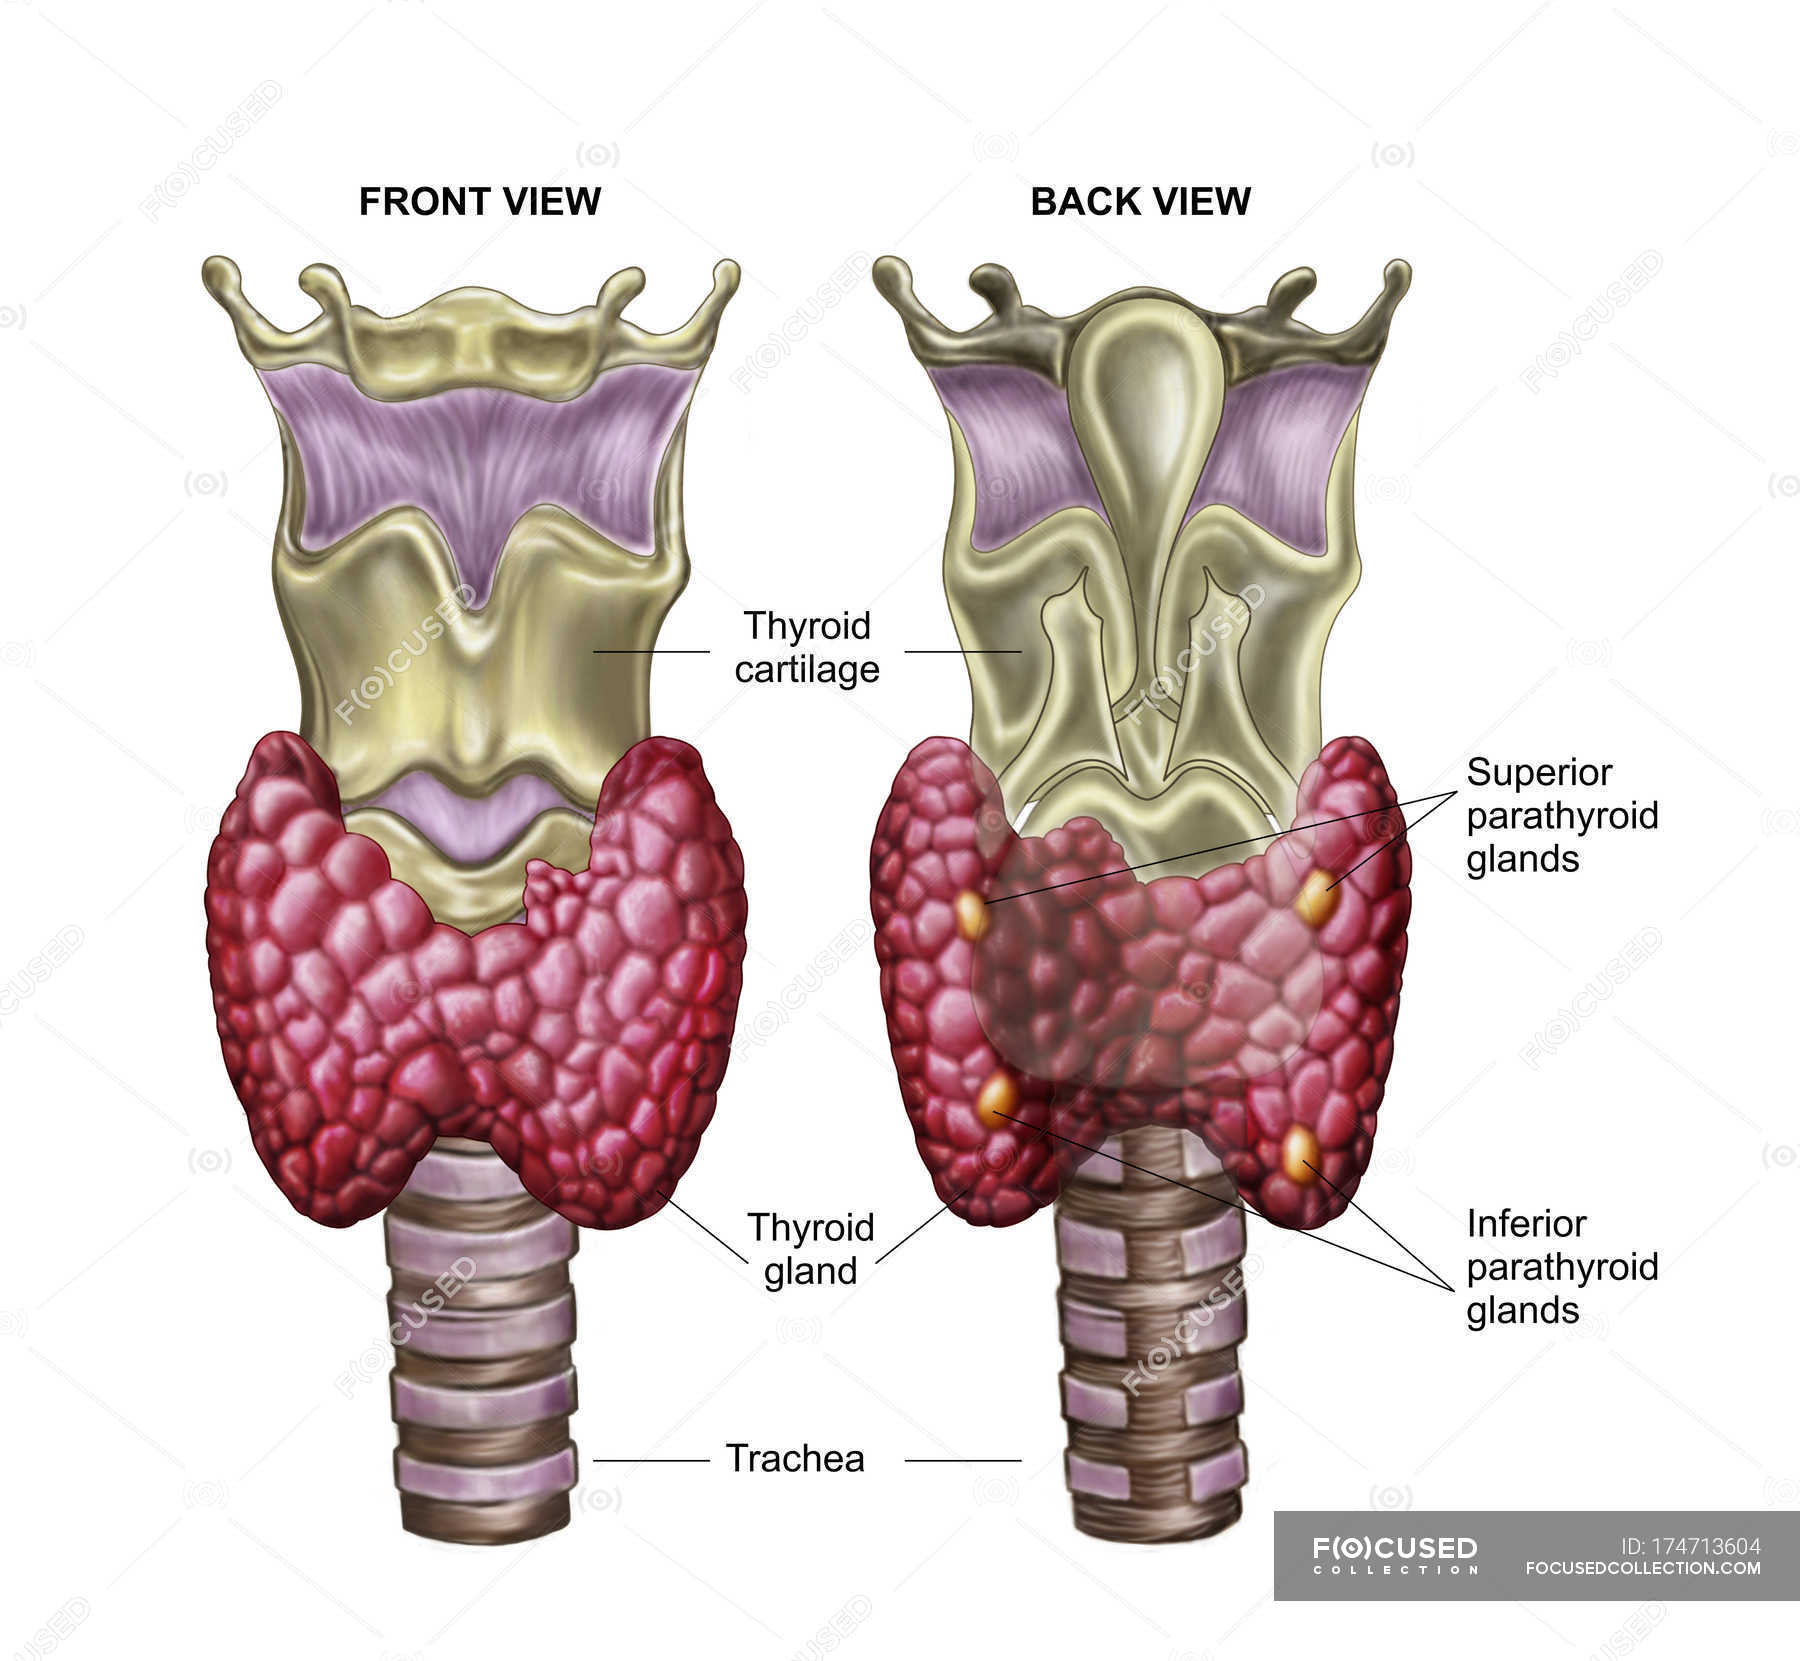

Le carbimazole, médicament très utilisé en Europe, est converti en méthimazole dans l’organisme. Page 1 sur 1: Poster un nouveau sujet: Auteur Message; tender. En pratique : Devant la fréquence des dysthyroïdies (4% à 25%) : Doser la TSH trimestriellement puis . Elle fabrique deux types d’hormones – la T3 et la T4 – qui tout à la fois régulent le métabolisme des cellules de notre corps ; contrôlent l’énergie musculaire, l’humeur et la température du corps ; augmentent le rythme .Le centre de référence des maladies rares de la réceptivité hormonale a été sollicité à plusieurs reprises, et de nombreux cliniciens ont été interpellés pour des bilans .Le diagnostic de l’hypothyroïdie est le plus souvent établi par le médecin traitant, en collaboration avec des médecins spécialistes (endocrinologue, radiologue. Elle est constituée de deux lobes, de part et d’autre du larynx. Ils diminuent la production d’hormones par la thyroïde. Lors de l’utilisation des hormones thyroïdiennes, une petite partie de leur iode est libérée et retourne à la thyroïde où elle est réutilisée pour fabriquer d’autres hormones thyroïdiennes. Sa forme est celle d'un papillon dont les deux ailes (les lobes) sont symétriques, et situées contre les . La maladie disparaît généralement spontanément . Cortisone et soleil.

Une suractivité anormale de la thyroïde entraîne, elle, de la nervosité, des sautes d’humeur, de l’insomnie, une transpiration excessive ou encore de la tachycardie.Tous ces maux caractérisent une hypothyroïdie. Réguler la température du corps, son poids, sa force musculaire. En cas d'hyperthyroïdie avec saillie des globes oculaires (maladie de Basedow le plus souvent), un traitement médical est d'abord tenté, en administrant pendant 18 mois un médicament capable de freiner l'activité de la glande. Contrôler la pression artérielle et le rythme cardiaque. Des molécules proches des hormones naturelles. Il palpe le cou.Un dérèglement thyroïdien se caractérise par un fonctionnement anormal de la thyroïde, une glande située à la base du cou.La thyroïde est une glande située en bas du cou, se présentant sous forme de deux lobes, à l’image de deux ailes d’un papillon, reliées par un isthme. Toutefois, si vous utilisez une approche méthodique et comprenez la signification de chaque test, vous saurez si vous avez ou non un problème de thyroïde et, le cas échéant, de quoi il s'agit.Il existe deux hormones thyroïdiennes : T4 : Thyroxine (également appelée tétraiodothyronine) T3 : Triiodothyronine. Localisation de la thyroïde.L’iode est un nutriment crucial pour le bon fonctionnement de notre glande thyroïde.La thyroïde est une glande située en dessous de la pomme Adam, dans la partie antérieure du cou.

agit en synergie avec les hormones thyroïdiennes au niveau des récepteurs cellulaires. Découvrez en quoi consiste l’hyperthyroïdie. La glande thyroïde, située dans le cou devant la trachée, pèse environ 30 g quand il n'existe pas de pathologies associées, et sécrète des hormones thyroïdiennes sous l'action d'une hormone hypophysaire : la thyréostimuline (TSH).06 décembre 2023.

March 14, 2023.La glande thyroïde est située à la base du cou, sous la peau. Ces hormones jouent un rôle vital dans diverses fonctions corporelles, notamment la croissance, le métabolisme énergétique et le . « Dans la plupart des cas, les médicaments contre la dysthyroïdie sont suffisants pour calmer cette inflammation générale » , . Les hormones stimulent l’activité d’autres cellules ou tissus.L’hyperthyroïdie résulte d’une hyperactivité thyroïdienne qui entraîne une élévation des taux d’hormones thyroïdiennes et une accélération des fonctions vitales de l’organisme. Validé par le collège . Aliments et compléments nutritionnels peuvent améliorer le fonctionnement de la thyroïde, réduire les déficits en nutriments associés à l'hypothyroïdie et éradiquer certains symptômes.Effets secondaires. Habituellement, elle n’est pas palpable.La thyroïde capte l’iode et l’intègre dans ses cellules pour la synthèse des hormones thyroïdiennes. Contre-indications. Un suivi régulier des taux de TSH et d’hormones thyroïdiennes, associé à un ajustement du dosage de Lévothyrox si nécessaire, peut . Chez certains patients, les yeux retrouvent leur état habituel sans séquelles et ne nécessitent pas de traitement chirurgical.Dans les cas modérés ou graves, les médecins peuvent recommander la prise de corticoïdes, tels que la prednisone, dont la dose est progressivement diminuée sur 6 à 8 . Cette hormone permet à la thyroïde de produire les hormones thyroïdiennes T3 et T4.

Présentation de la thyroïde

Maladies de la thyroïde et des parathyroïdes